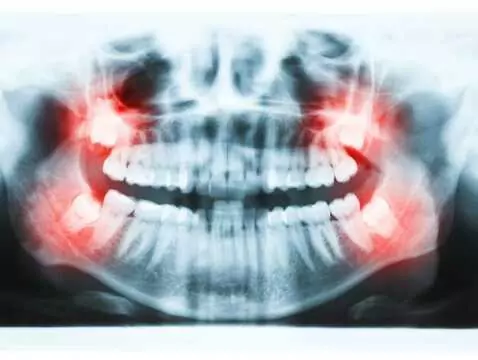

La sortie des dents de sagesse s'accompagne généralement de douleurs. La gêne et la sensation désagréable lors de la sortie des huit peuvent s'atténuer d'elles-mêmes, mais dans certains cas, un...